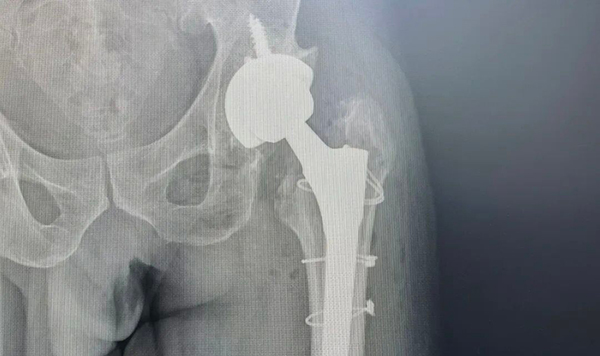

60岁的范先生在家意外摔倒致左髋部疼痛,无法活动。在当地医院检查后提示左股骨骨折,采用保守治疗方式给予止痛。后期,患者前往第一医院北院骨三科寻求进一步治疗。科室副主任李春会在详细了解患者病情后,诊断为左侧股骨头缺血性坏死合并左股骨转子下骨折,决定采用“髋关节后外侧入路”方式,为其实施左侧人工全髋关节置换+钛缆内固定术进行治疗。整台手术仅用时1小时30分,出血量100ml。术后第二天,患者在医护人员的帮助下即可下床活动,恢复迅速。

如今,人工全髋关节置换术的成熟应用,早已成为终末期髋关节疾病的“金标准”。该技术能彻底解除患者因关节软骨磨损、骨质增生或股骨头坏死引发的持续性疼痛与活动剧痛,使其无需依赖止痛药,轻松恢复安稳睡眠、久坐等日常功能,更能重建髋关节生理功能,让行动受限成为过去。对于范先生这类股骨头坏死合并关节外骨折的复杂病例,其手术步骤繁琐、操作难度大,北院骨三科团队针对性选用后外侧入路方式,兼顾髋关节置换与骨折内固定的切口需求,实现术野充分暴露、精准直达病灶。更重要的是,牢固的内固定让患者术后可尽早开展功能锻炼,大幅压缩住院与康复周期,为早期安全康复筑牢基础,真正实现“最小创伤、最大疗效”的微创目标,如同“精准拆弹”般完成高质量关节重建。